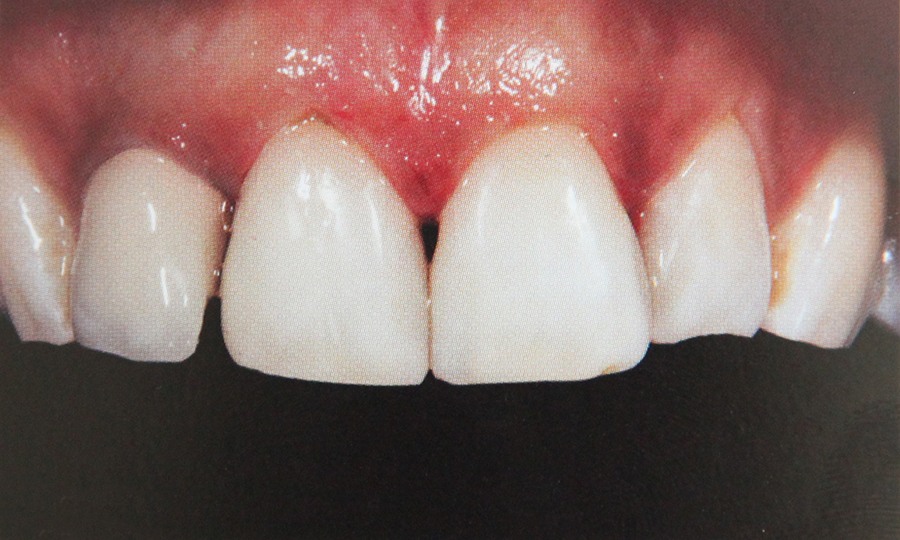

Tehnicile adezive directe de lucru cu materiale bazate pe rasini composite reprezinta o modalitate excelenta de restaurare estetica si minim invaziva a dintilor frontali. Obtinerea rezultatelor estetice asteptate este legata indesolubil de alegerea si utilizarea corecta, conform indicatiilor, a materialelor si tehnicilor de lucru adecvate, fiecarei situatii clinice.